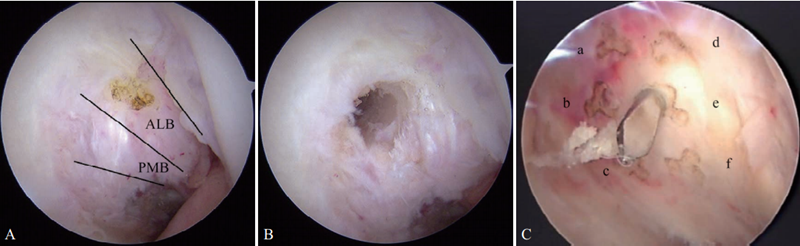

1.关节镜下探查

首先在关节镜下探查确定PCL断裂情况(图1)。单束重建是多数学者最常用的手术。取腘绳肌腱编制成4股移植物,探查时尽量保留PCL残端。

图1 关节镜下PCL断裂情况

A.PCL从胫骨止点断裂;B. PCL从股骨止点断裂;C. PCL断裂后松弛失去张力